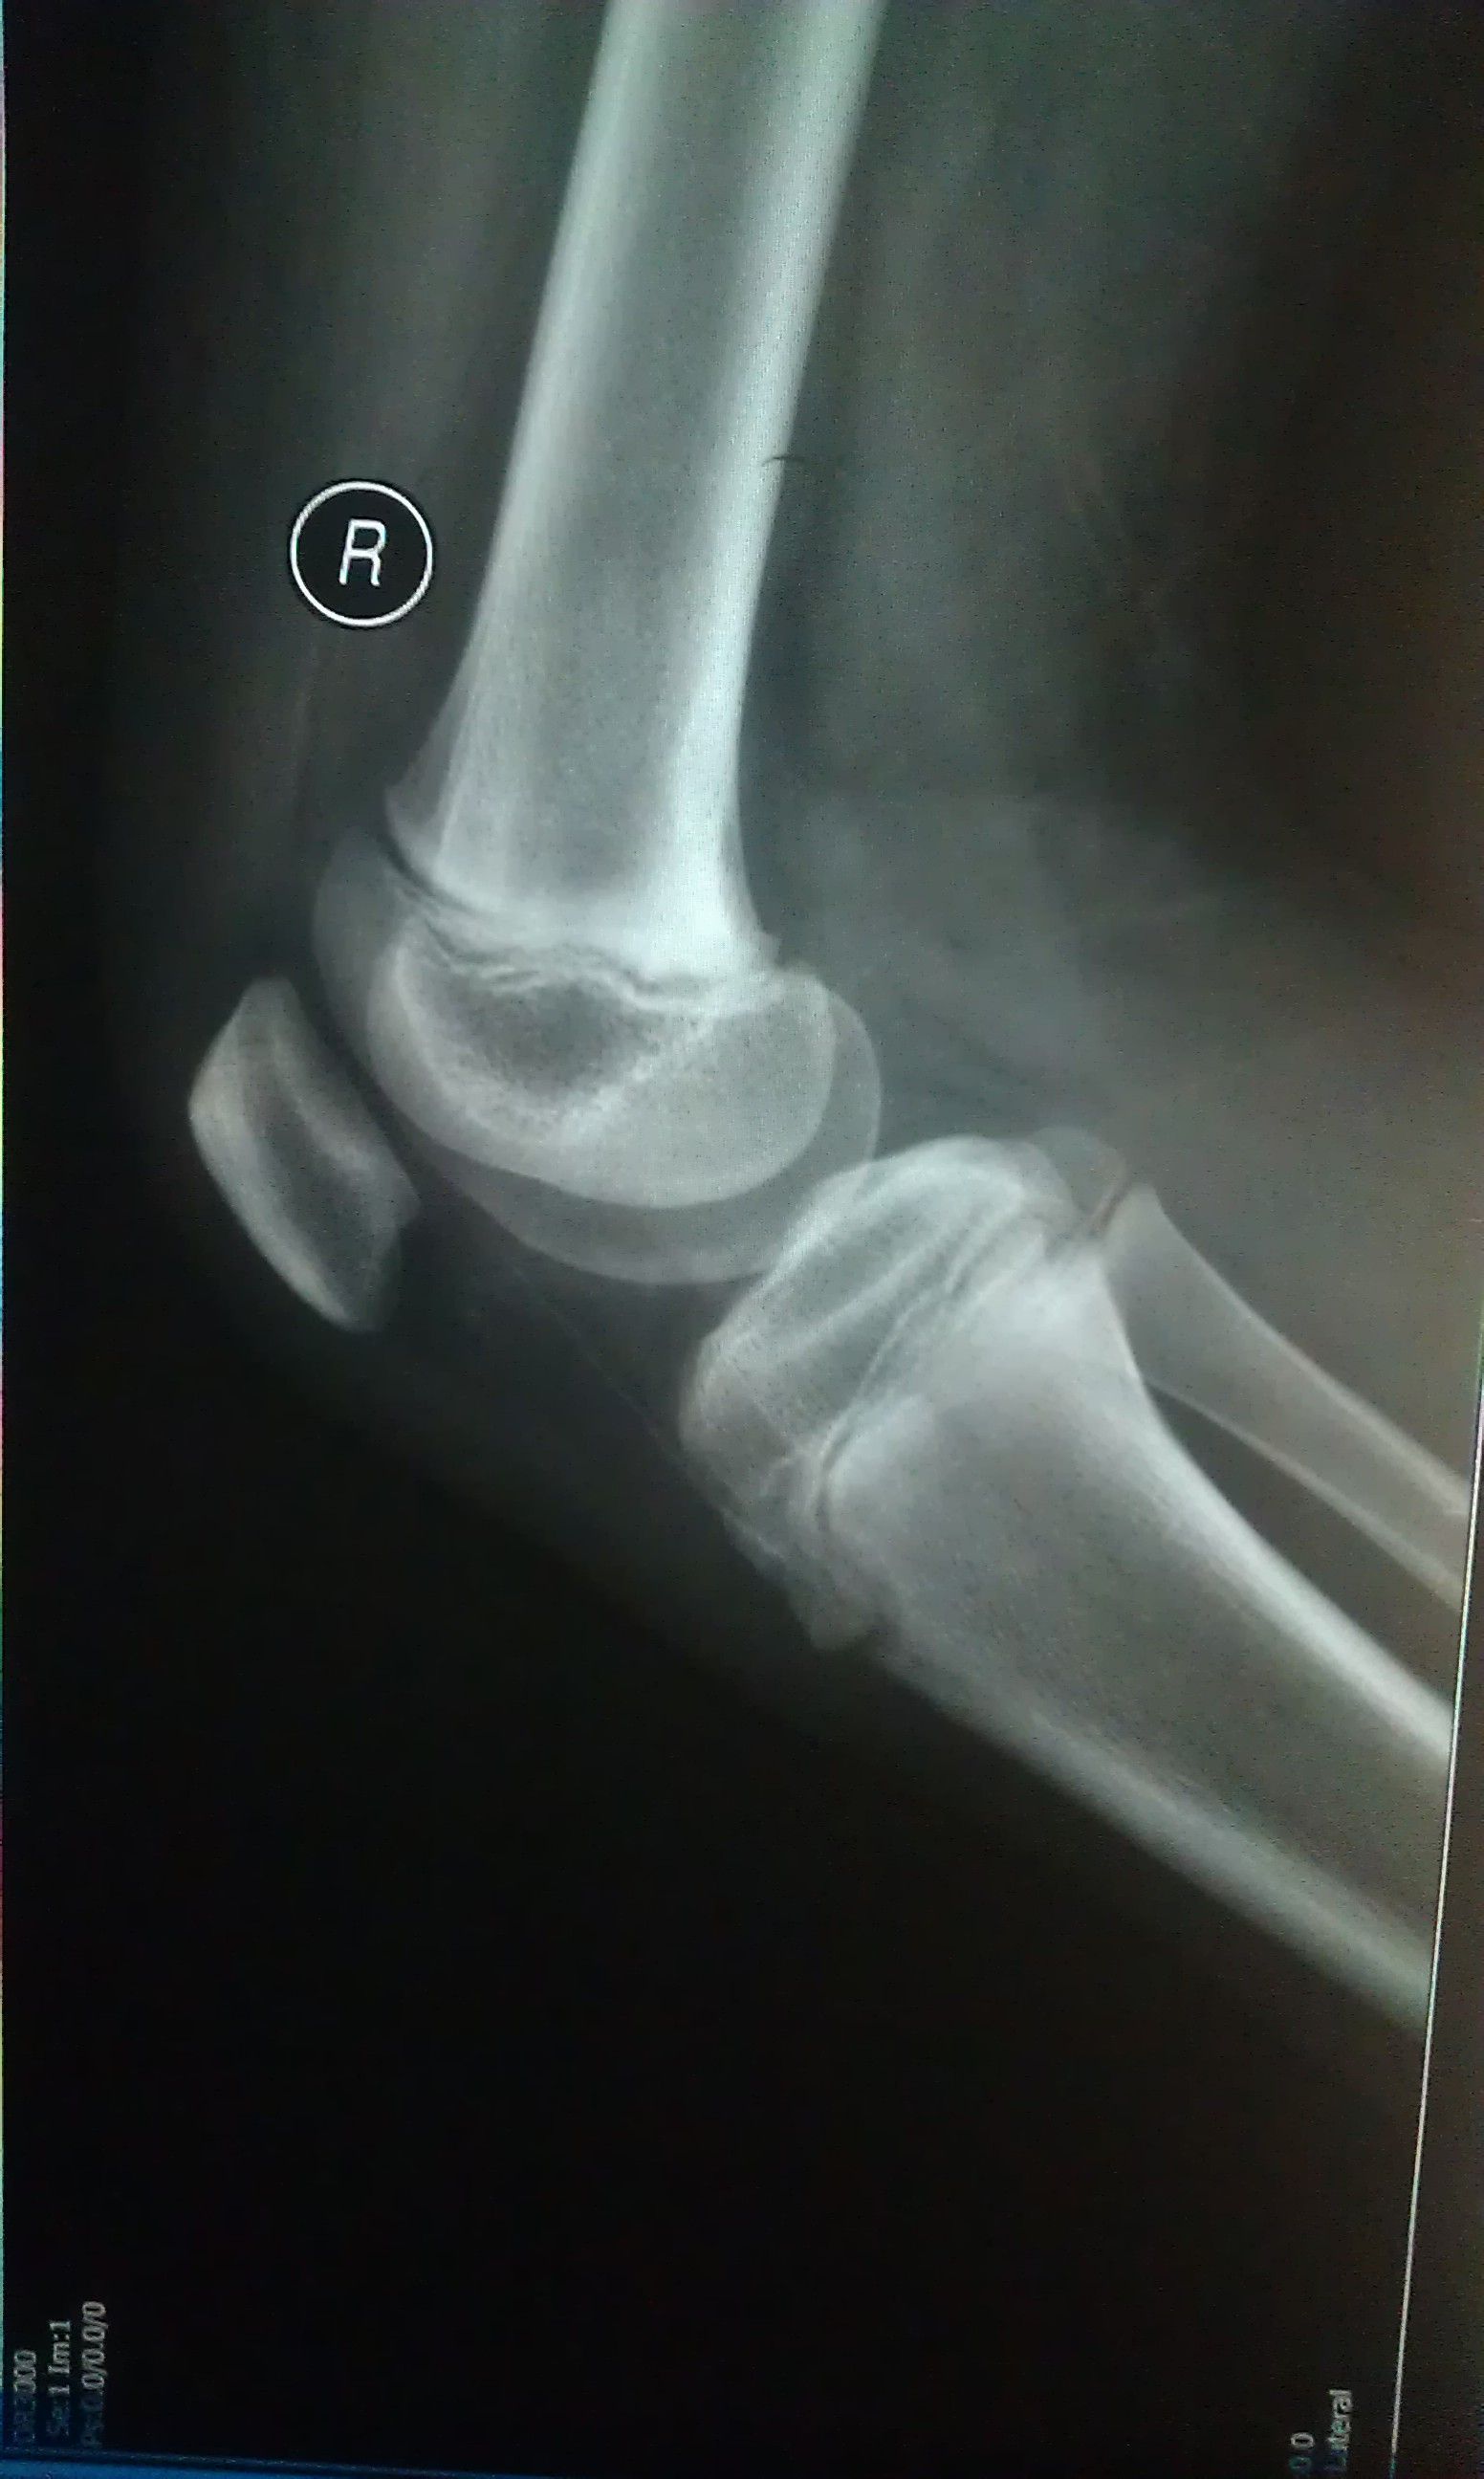

我小孩在近一个多月 下蹲 上站时 膝盖下面总是疼(按他说的意思我在图3标了一下),一开始是右腿,现

在是两条腿的相同部位都有这现象,一边疼的时候去医院看过,也拍了X片(见图1、2),医院医生没说什么,开了药和膏药,说吃完了还疼再去给他看,是不是风湿性关节炎(病历和药见图4)。我们家长不放心这医生,在这想请在线医生帮帮忙,分析一下我孩子的X片 !不胜感激!